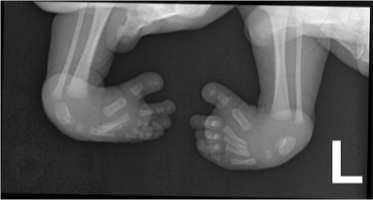

clubfeet/talipes equinovarus

what condition?

talipes equinovarus

clubfeet is also called ________________

adductus

varus

equinus (limited dorsiflexion)

positioning of club feet/talipes equinovarus:

forefoot ____________

hindfoot ____________

ankle ______________